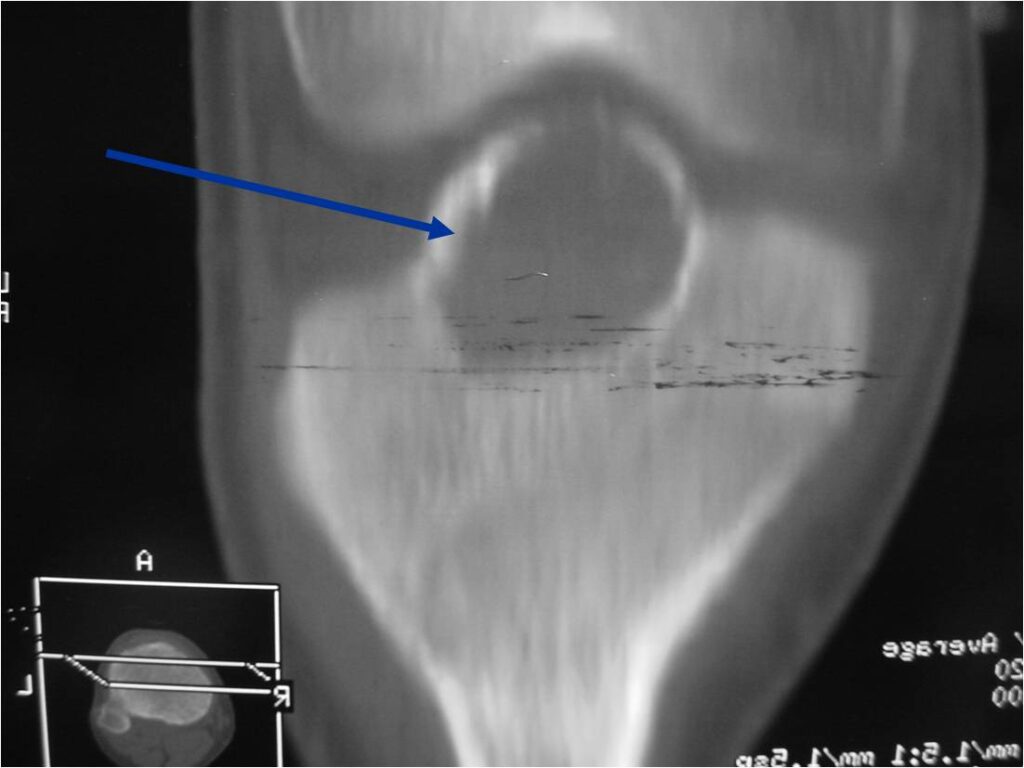

Radiographic Presentation

- Presents as a highly defined/well circumscribed geographic oval/round lytic defect

- Surrounded by rim of sclerotic bone

- Usually in epiphyseal region

- Lesion ranges from 3 cm to 6 cm diameter

- Usually radiolucent

- May have fine trabeculae and irregular calcifications

- Calcifications are often better detected with a CT scan but are not uniformly present

- Lesions may expand the bone and new periosteal bone may form

- Bony end plate, cortex, bone contour are unaffected

- (Plain x-ray appearance)

- Geographic lytic lesion IA/IB margin of sclerosis

- Usually Eccentric more often than Central in the bone

- Rarely expansile (rarely penetrates the cortex)

- Calcified chondroid matrix 30%-50% of cases

- Often better detected with a CT Scan

- Periosteal Reaction 30-50% of cases

- Usually occurs in Adjacent Diaphysis/Metaphysis since epiphysis is intraarticular and not surrounded by periosteum